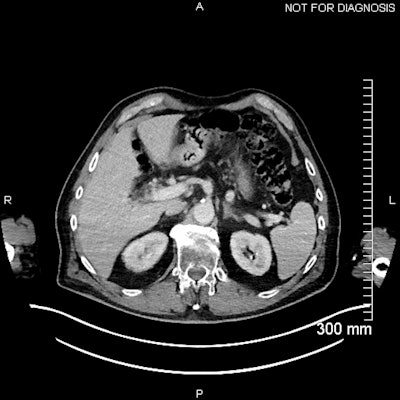

(Above) Fused axial image demonstrates uptake in the celiac ganglia. (Below) Corresponding CT scan. The celiac ganglia are visible. All figures courtesy of Dr. Jonathan Hunter, Dr. Jane Burns, and Prof. Martin O’Connell and presented at ECR 2025.

The physiological uptake of PSMA ligands in various normal tissues is an important pitfall in PSMA-targeted imaging, they continued. In particular, uptake in sympathetic trunk ganglia can pose challenges to nuclear medicine readers and may mimic lymph nodes. Also, cervical chain and coeliac ganglia may demonstrate higher uptake with F-18 PSMA.